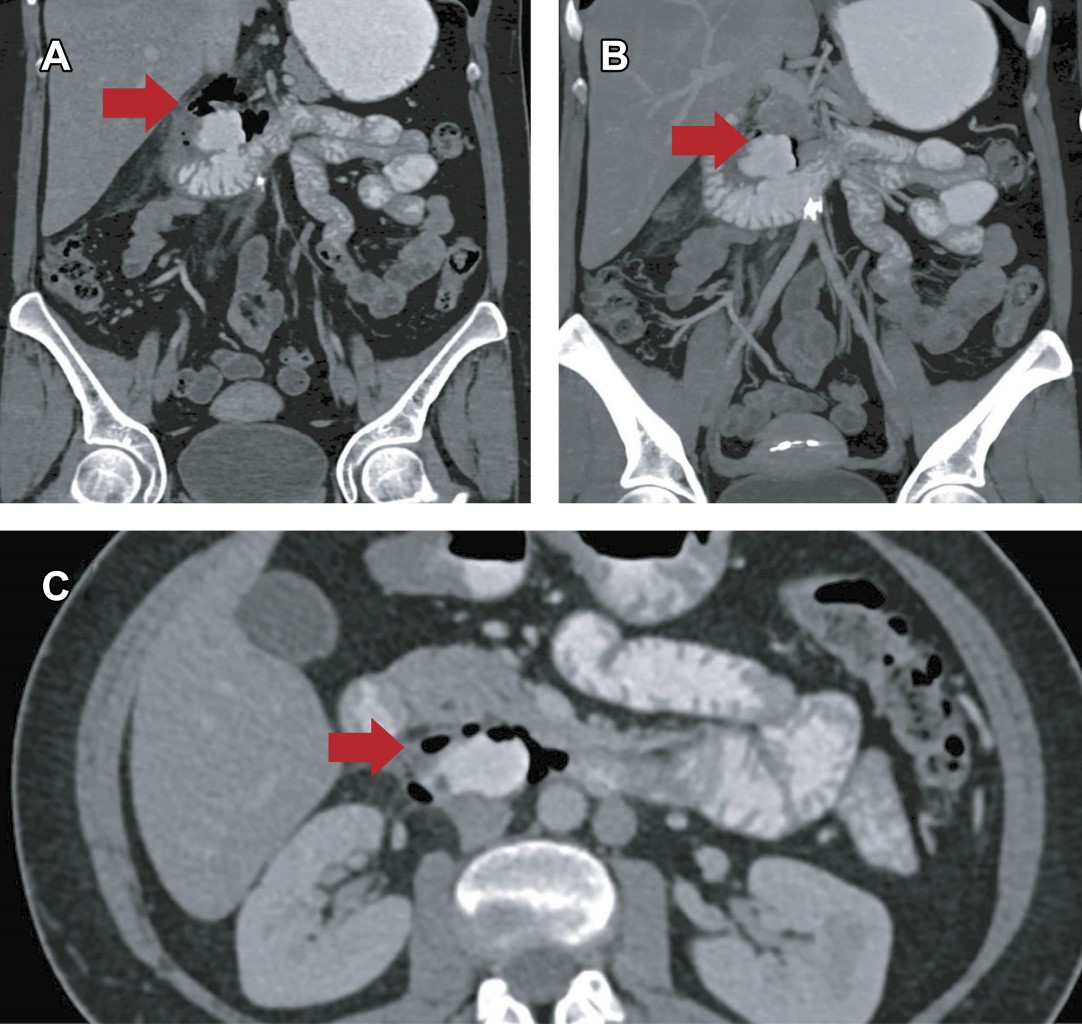

Paciente femenino de 50 años, con antecedente de hipertensión, evento isquémico transitorio y enfermedad por reflujo gastroesofágico; con dos panendoscopias previas. Ingresa a urgencias refiriendo dolor abdominal de cuatro días de evolución, incomodidad postural y distensión abdominal. En la exploración física: peso 63.5 kg, talla 166.3 cm; índice de masa corporal (IMC) 23 kg/m2. Frecuencia cardiaca (FC) 85 lpm, frecuencia respiratoria (FR) 21 rpm, temperatura 35.7 °C, saturación de oxígeno 92%, presión arterial (TA) 113/66 mmHg. Neurológicamente íntegra; escala de Glasgow 15 puntos. Cardiopulmonar sin compromiso. Abdomen blando, depresible, con dolor a la palpación superficial y profunda del hipocondrio derecho (escala visual analógica [EVA] 8/10), rebote positivo, sin datos de irritación peritoneal; con disminución en la peristalsis. Se solicitan estudios de laboratorio e imagen, así como abordaje por cirugía general. Los resultados de laboratorio indicaron leucocitosis, elevación de los reactantes de fase aguda (Proteína C Reactiva [PCR], Procalcitonina [PROCA]) y desnutrición proteico-calórica/hipoalbuminemia (Tabla 1), en tanto que la tomografía abdominal evidenció divertículo duodenal con perforación contenida (Figura 1).

Por la ausencia de fuga del medio de contraste al espacio extraluminal, el tiempo de evolución y que la paciente se encontraba hemodinámicamente estable, se decide iniciar con manejo conservador, el cual consistió en la administración de nutrición parenteral (NP), con una distribución de carbohidratos 50%, aminoácidos 30% y lípidos 20%, antibioticoterapia de amplio espectro con ertapenem y fluconazol, tromboprofilaxis con enoxaparina y manejo analgésico con paracetamol y antiinflamatorios no esteroideos.

Tras seis días de vigilancia manteniendo presión arterial media (TAM) entre 65-70 mmHg, FC 60-75 lpm, FR 14-16 rpm, saturación de oxígeno > 94%, temperatura 36-36.8 °C, con NP y clínicamente asintomática, se realizó control tomográfico, en donde se observó divertículo con menor cantidad de aire extraluminal (Figura 2), mejoría en laboratorios (Tabla 1) y ausencia de síntomas, por lo que se inició dieta líquida a tolerancia, con progresión a dieta específica, con disminución progresiva de NP. Se avanzó a dieta blanda, sin grasas ni irritantes; una vez completados siete días de tratamiento antibiótico, se suspendió ertapenem y fluconazol. A los diez días, la paciente presentó mejoría en sintomatología abdominal, adecuada evolución clínica y tolerancia al 100% de sus requerimientos nutricionales, por lo que fue dada de alta.

Actualmente, a cuatro meses del evento inicial, la paciente se ha mantenido estable; sus laboratorios están en la normalidad (Figura 1) y los principales síntomas que presenta son secundarios a enfermedad por reflujo gastroesofágico, razón por la que se encuentra en tratamiento con inhibidores de la bomba de protones (IBP), procinético y protector de mucosa.

El diagnóstico oportuno de una perforación diverticular resulta crucial para determinar un manejo conservador. Para identificar un divertículo duodenal y una perforación de este tipo de divertículos se requiere un buen examen clínico, pruebas de laboratorio, así como pruebas de imagen con cortes finos (tomografía computarizada [TC]). La TC es la prueba de referencia para el diagnóstico de divertículo duodenal perforado.3 Los hallazgos radiológicos a tomar en cuenta son: engrosamiento de la pared duodenal ≥ 4 mm, estriación de grasa mesentérica y aire/líquido extraluminal o retroperitoneal.3 De acuerdo con lo presentado, nuestra paciente no mostró datos de irritación peritoneal debido a que el crecimiento estaba a nivel retroperitoneal, lo que causaba síntomas vagos; el diagnóstico se realizó mediante el protocolo de TC.6 La ausencia de fuga de contraste oral demostró que el divertículo estaba contenido; el riesgo de someter a la paciente a una cirugía de urgencia era mayor que los beneficios que podía ofrecer.3